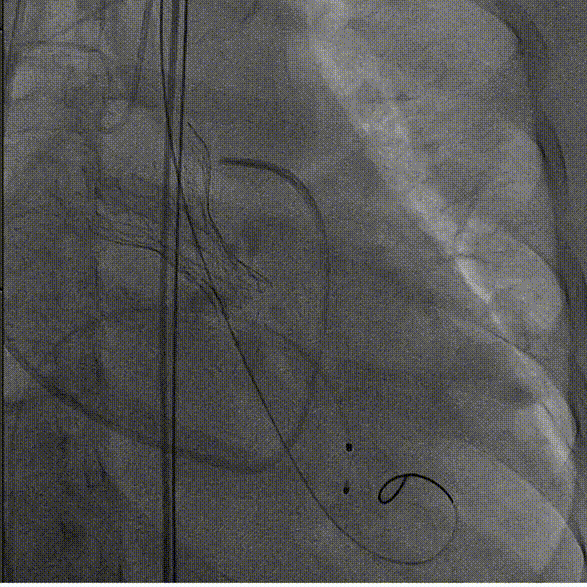

3.TaurusElite AV26号瓣膜定位及释放。瓣膜初始定位瓣下2mm,开花后120次起搏,释放到工作位后造影显示锚定充足,位置良好,冠脉未见遮挡,继续缓慢旋转手柄,瓣膜逐一脱钩,顺利释放。

瓣膜初始定位

瓣膜释放过程

瓣膜脱钩